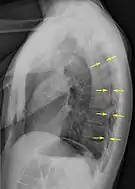

Chest X-ray

A plain chest radiograph, ideally with the X-ray beams being projected from the back (posteroanterior, or "PA"), and during maximal inspiration (holding one's breath), is the most appropriate first investigation.[25] It is not believed that routinely taking images during expiration would confer any benefit.[26] Still, they may be useful in the detection of a pneumothorax when clinical suspicion is high but yet an inspiratory radiograph appears normal.[27] Also, if the PA X-ray does not show a pneumothorax but there is a strong suspicion of one, lateral X-rays (with beams projecting from the side) may be performed, but this is not routine practice.[14][18]

Lateral inspired X-ray at the same time, more clearly showing the pneumothorax posteriorly in this case

The size of the pneumothorax (i.e. the volume of air in the pleural space) can be determined with a reasonable degree of accuracy by measuring the distance between the chest wall and the lung. This is relevant to treatment, as smaller pneumothoraces may be managed differently. An air rim of 2 cm means that the pneumothorax occupies about 50% of the hemithorax.[14] British professional guidelines have traditionally stated that the measurement should be performed at the level of the hilum (where blood vessels and airways enter the lung) with 2 cm as the cutoff,[14] while American guidelines state that the measurement should be done at the apex (top) of the lung with 3 cm differentiating between a "small" and a "large" pneumothorax.[28] The latter method may overestimate the size of a pneumothorax if it is located mainly at the apex, which is a common occurrence.[14] The various methods correlate poorly but are the best easily available ways of estimating pneumothorax size.[14][18] CT scanning (see below) can provide a more accurate determination of the size of the pneumothorax, but its routine use in this setting is not recommended.[28]